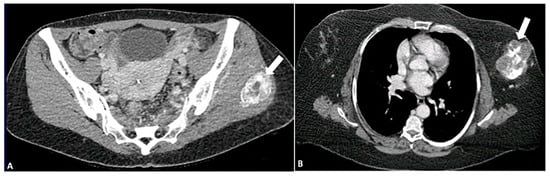

4.1. Adipocytic Tumors

- Peterson, J.J.; Kransdorf, M.J.; Bancroft, L.W.; O’connor, M.I. Malignant fatty tumors: Classification, clinical course, imaging appearance and treatment. Skelet. Radiol. 2003, 32, 493–503. [Google Scholar]

- Kransdorf, M.J.; Bancroft, L.W.; Peterson, J.J.; Murphey, M.D.; Foster, W.C.; Temple, H.T. Imaging of fatty tumors: Distinction of lipoma and well-differentiated liposarcoma. Radiology 2002, 224, 99–104. [Google Scholar]

- Murphey, M.D.; Arcara, L.K.; Fanburg-Smith, J. Imaging of musculoskeletal liposarcoma with radiologic-pathologic correlation. Radiographics 2005, 25, 1371–1395. [Google Scholar]

- Henze, J.; Bauer, S. Liposarcomas. Hematol. Oncol. Clin. 2013, 27, 939–955. [Google Scholar] [CrossRef]

- Toms, A.P.; White, L.M.; Kandel, R.; Bell, R.S. Low-grade liposarcoma with osteosarcomatous dedifferentiation: Radiological and histological features. Skelet. Radiol. 2003, 32, 286–289. [Google Scholar]

- O’Regan, K.N.; Jagannathan, J.; Krajewski, K.; Zukotynski, K.; Souza, F.; Wagner, A.J.; Ramaiya, N. Imaging of liposarcoma: Classification, patterns of tumor recurrence, and response to treatment. Am. J. Roentgenol. 2011, 197, W37–W43. [Google Scholar] [CrossRef]